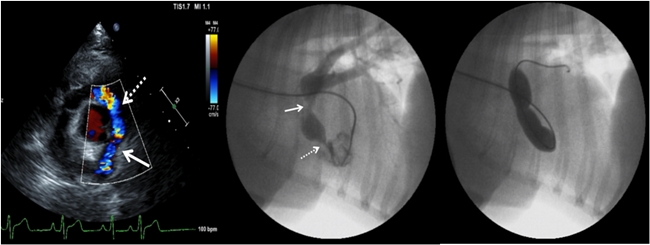

심장초음파 영상 (왼쪽)과 심장조영(가운데)을 통하여 확인한 후,

풍선판막성형술을 통해 폐동맥 협착부위를 확장하고 있는 모습(오른쪽)

폐동맥협착증을 앓고 있던 1년 9개월령 프렌치불독 품종 환견과 대동맥하협착증을 앓고 있던 9개월령 포메라니언 품종 환견은 선천적 심장질환으로 인해 어렸을 때부터 기절, 운동불내성, 청색증 등의 증상으로 고통 받았다.

특히 프렌치불독 환견의 경우 폐동맥협착증과 함께 난원공개존증(PFO)이라는 선천성 심장기형을 함께 가지고 있어 교정이 쉽지 않았다.